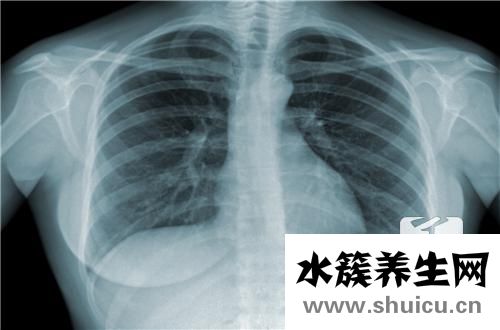

人們認(rèn)為結(jié)核病的類型很多,更常見(jiàn)的是結(jié)核病。 一旦患上肺結(jié)核,患者最容易出現(xiàn)咳嗽癥狀,并且經(jīng)常伴有低燒癥狀和疾病惡化,患者會(huì)咳嗽得更厲害,并且會(huì)有胸腔積液,患者的吸入 明顯異常,這表明結(jié)核病的巨大不利影響,以下是結(jié)核病預(yù)防專業(yè)知識(shí)的詳細(xì)說(shuō)明。

結(jié)核病是由結(jié)核菌入侵身體后造成的一種嚴(yán)重威脅人類身心健康的傳染性疾病,具備極強(qiáng)的感染性,故大家對(duì)結(jié)核病造成了較強(qiáng)的心理恐懼。伴隨著科技進(jìn)步的進(jìn)度,早已研發(fā)出十?dāng)?shù)種合理的抗結(jié)核藥物,要是初期發(fā)覺(jué),靠譜醫(yī)治,是徹底能夠痊愈的。結(jié)核菌能夠入侵身體一切人體器官,換句話說(shuō)身體的各種各樣人體器官都能夠產(chǎn)生結(jié)核病,但結(jié)核菌關(guān)鍵根據(jù)人體的呼吸道開(kāi)展散播,因此在身體感染結(jié)核菌后產(chǎn)生肺結(jié)核者占絕大部分。因而,“防治結(jié)核病,從我做起”。